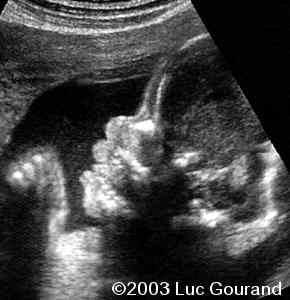

The following images were obtained in from second trimester fetus. The head demonstrated a cloverleaf skull, frontal bossing, proptosis

Radiohumeral ankylosis was seen at the level of the arm, the thumb and toes are broad.

So the diagnostic clues for Pfeiffer type II were:

• cloverleaf skull,

• severe proptosis,

• elbow synostosis,

• broad thumb and great toes,

• abnormal vertebrae.